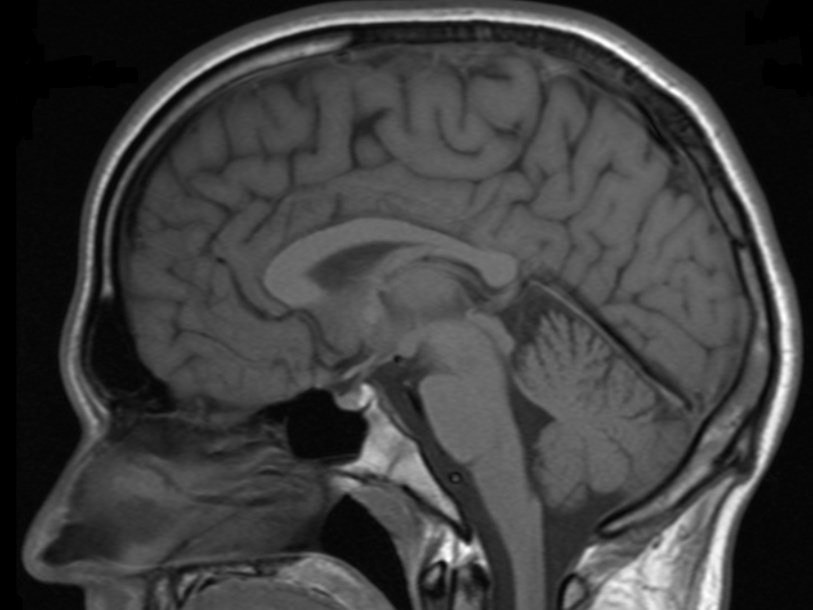

Рассеянный склероз относится к аутоиммунным заболеваниям, при которых деятельность Т-клеток иммунной системы по каким-то причинам направляется не против патогенов, а против здоровых тканей организма. При этой болезни разрушаются миелиновые оболочки нервных волокон в спинном и головном мозге, что ведет к постепенному нарастанию неврологических нарушений: потере кожной чувствительности, нарушениям зрения, тремору, нарушениям координации движений и так далее. Полностью излечить рассеянный склероз современные врачи не могут. Пока они в состоянии только замедлить развитие болезни.